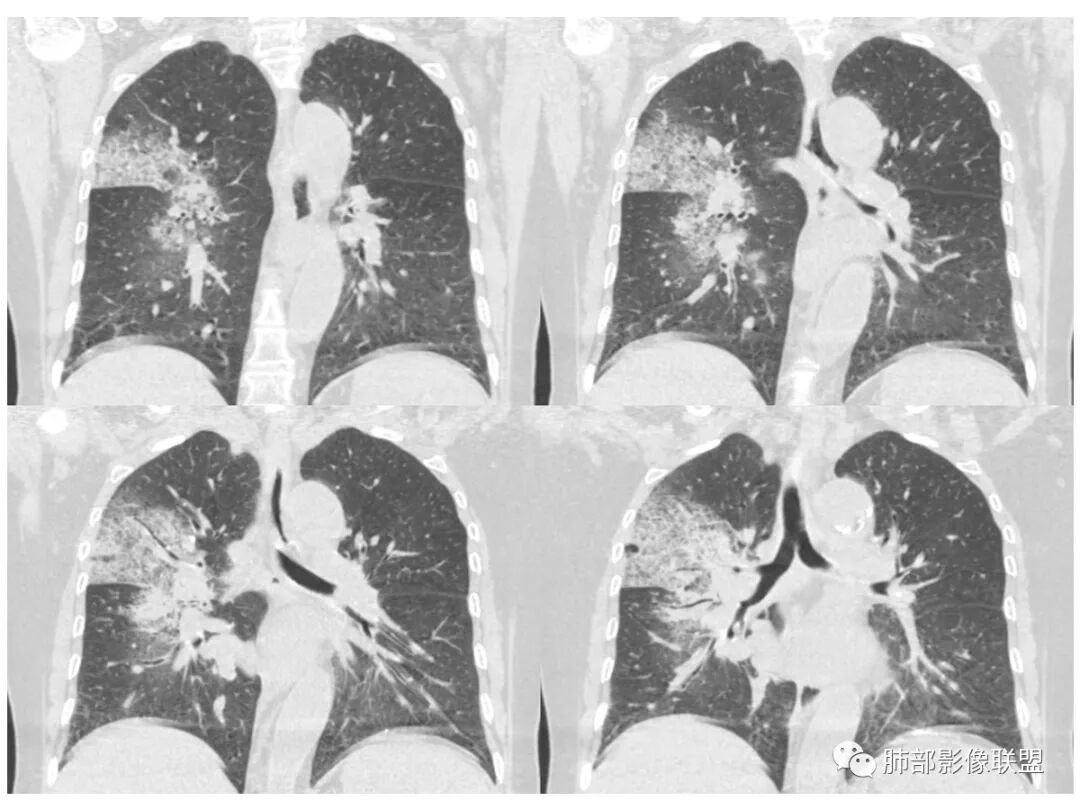

右肺上叶大片状阴影,内见僵硬的支气管,部分支气管轻度扩张,内见一空洞和液平,病灶边缘可见磨玻璃影,首先考虑恶性病变,粘液性腺癌伴感染可能。

老年女性,慢性病史,白色痰液,量多,病灶起于胸膜下,实性加磨玻璃,磨玻璃边缘偏轻,跨叶生长,病灶内可见枯树枝,考虑肺炎型肺癌。

老年女性,右肺上叶大片实变及磨玻璃密度影,磨玻璃边缘清晰,内可见小叶间隔增厚,内可见空洞,似可见分隔,叶间裂局部膨隆,纵膈窗,没有增强,枯树枝不明显,肺炎型肺癌可能,鉴别大叶性肺炎,结核?

胸CT:右肺上叶实变内可见支气管充气征,近端支气管狭窄,远端扩张,周围可见毛玻璃影,右肺中叶支气管闭塞,并可见气道壁钙化,右肺中叶体积缩小,实变内可见空洞,并可见气液平面,空洞周围可见毛玻璃样影,右肺下叶支气管开口狭窄,右肺门淋巴结肿大。纵隔窗可见病灶与壁层胸膜间隙增宽,考虑良性病变-----感染性病变------TB?

老年女性,无诱因咳嗽咳痰,白色粘液痰,抗炎治疗无好转,右肺多叶磨玻璃影,其内见枯树枝征,磨玻璃边界清,中间见实变影,且部分实变影内见空洞或局部支气管扩张,内壁光整,无纵隔淋巴结肿大,常规考虑粘液性腺癌,感染性病变待排,细菌性的排除,白细胞不高,不太支持,建议支气管镜检。

1.右上肺大片状影,周围有磨玻璃影,支气管截断征、枯枝征、远端支气管充气征,可见多个大小不等囊泡(支气管阻塞活瓣作用形成),病灶有少许收缩力感,叶间裂被稍牵拉内移;

病史老年女,白痰;影像实变,ggo多数边界清,病灶下缘部分不清,枯树枝,支气管近端阻塞、僵硬,病灶跨叶;病灶内空洞,有液平;间质增厚有结节感;肺炎型肺癌大于干酪性肺炎。

老年女性,慢性病程,咳嗽伴白色粘液痰,无发热腹痛,糖尿病,白细胞及C反应蛋白不高,血沉快,铁蛋白高。胸部CT,右肺上叶大片状实变伴磨玻璃密度影,边界不清,边缘局部膨隆,叶裂弧形下坠,实变影宽基底与胸膜相贴;右肺下叶前基底段见类似病灶;右肺中叶不张并空洞形成,空洞内见气液平面;综合考虑右肺上叶及下叶肺炎型肺癌,右肺中叶结核。

老年女性,病史1月,右肺上中叶大片状影,跨叶,上叶为主,磨玻璃为主,边界模糊,部分实变,内见空洞影和液气平面,壁光滑,支气管开口狭窄,局部有扩张,右肺门淋巴结钙化,首先考虑感染性病变,结核可能,鉴别粘液腺癌。

白色粘液痰,枯树枝,支气管僵直,有空洞,磨玻璃,叶间裂膨隆、下坠,吴婧老师的肺炎型粘液性腺癌十大特点中占了好多条,所以考虑粘液腺癌,就差增强看看强化如何,血管如何了

患者老年女性,亚急性起病,胸部CT:右肺上叶大片实变,可内见坏死性空洞,可见mGGO,GGO边缘清晰,局部彭隆,内见支气管充气征,可惜没增强,粘液腺癌要考虑,但病灶明显是内朝外不支持,综合考虑结核,建议查痰找抗酸杆菌、气管镜

老年女性,咳白色粘液痰,右肺跨叶大片高密度影,密度不均匀,其内见支气管枯树征,有空洞,边缘部分清楚,叶间裂有下坠膨隆感。考虑粘液腺癌,鉴别干酪性肺炎